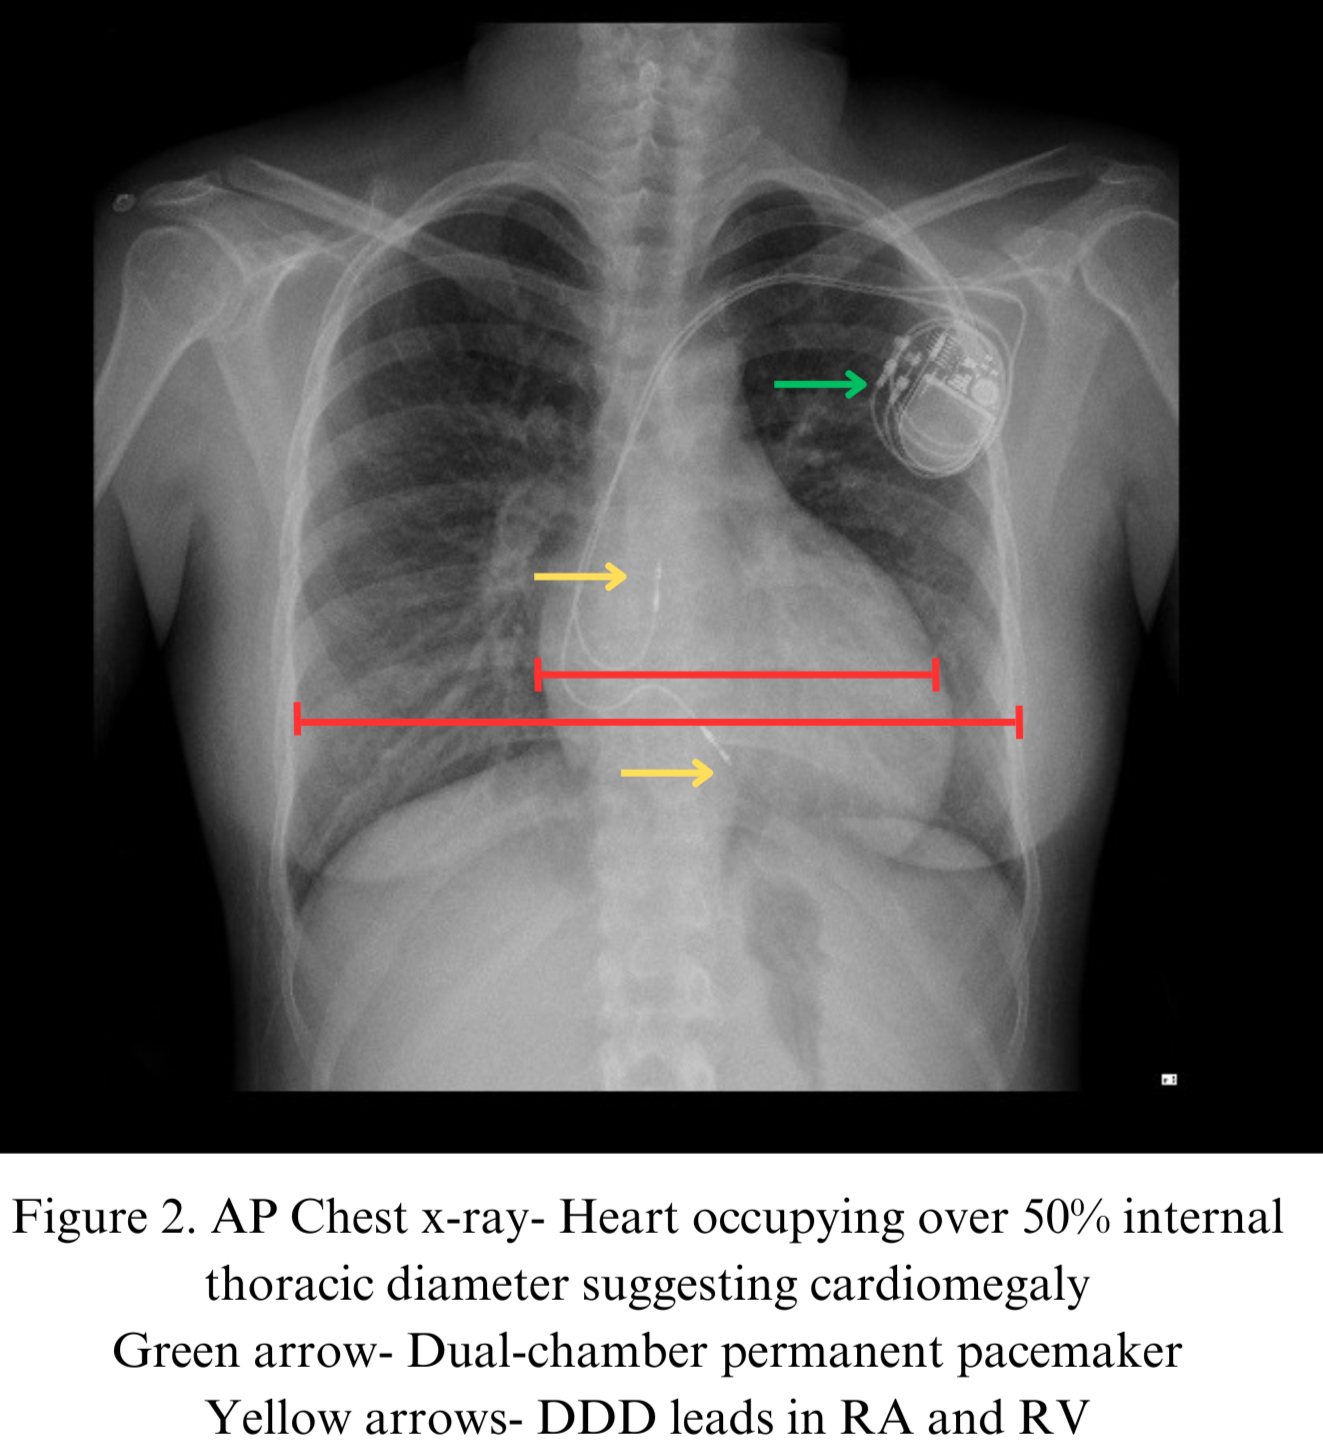

A 24-year-old primigravida at 35 weeks’ gestation with history of CCTGA presented with fatigue,bradycardia,and reduced fetal movements.Examination revealed bradycardia,cannon waves in the JVP,regular pulse,and varying first heart sound intensity without murmur.EKG showed CHB.Echocardiography revealed situs solitus with levocardia,AV and VA discordance,Ebstein-like systemic AV valve,moderate regurgitation,and reduced systemic ventricular EF.A temporary pacemaker was placed preoperatively,and an emergency cesarean was performed.On postoperative day 11,she had a cardiac arrest with seizure and was resuscitated.ECG showed CHB,narrow QRS escape rhythm,bradycardia-induced PMVT,deep Q waves in lead III,and absent Q waves in lateral leads(Fig.1).She was intubated,admitted to the cardiac ICU,and managed with temporary pacing.After stabilization,she underwent dual-chamber(DDD) permanent pacemaker implantation(Fig.2) and was discharged on medical therapy with dietary advice,pacemaker checks,and regular follow-up.